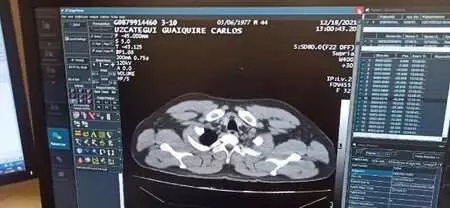

Yapılan ilk muayenenin ardından C.M.U.G., tedavisi için havalimanı emniyet şube müdürlüğü ekiplerinin kontrolünde hastaneye kaldırıldı. C.M.U.G'un hastanede yapılan tomografi kontrolünde mide ve bağırsaklarında 12 adet kapsül kokain tespit edilmesini üzerine ameliyata alındı.